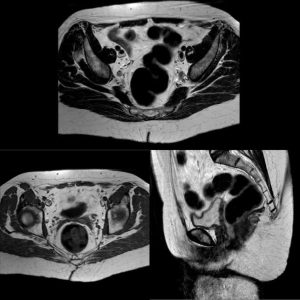

Tras 5 años en seguimiento, la paciente se encuentra asintomática con analítica rigurosamente normal y tomografía toraco-abdómino-pélvica y resonancia magnética pélvica sin datos de recidiva tumoral (ver imagen 3).

Imagen 3: Resonancia magnética pélvica a los 5 años tras tratamiento que no refleja datos de recidiva tumoral.